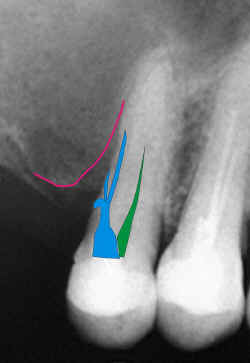

Esquema gráfico evidenciando ao leigo as alterações

visualizáveis na radiografia.

A

imagem é clara e o fato constitui erro odontológico, passível de responsabilização do

profissional.

perda do elemento dentário, se ocorrer constitui debilidade permanente de função de

acordo com o Código Penal Brasileiro (art 129).

O

profissional responsável pelo ocorrido pode ser acionado civilmente de acordo com o

Código Civil Brasileiro (art 1545), e por

inúmeros artigos do Código de Ética Odontológica |